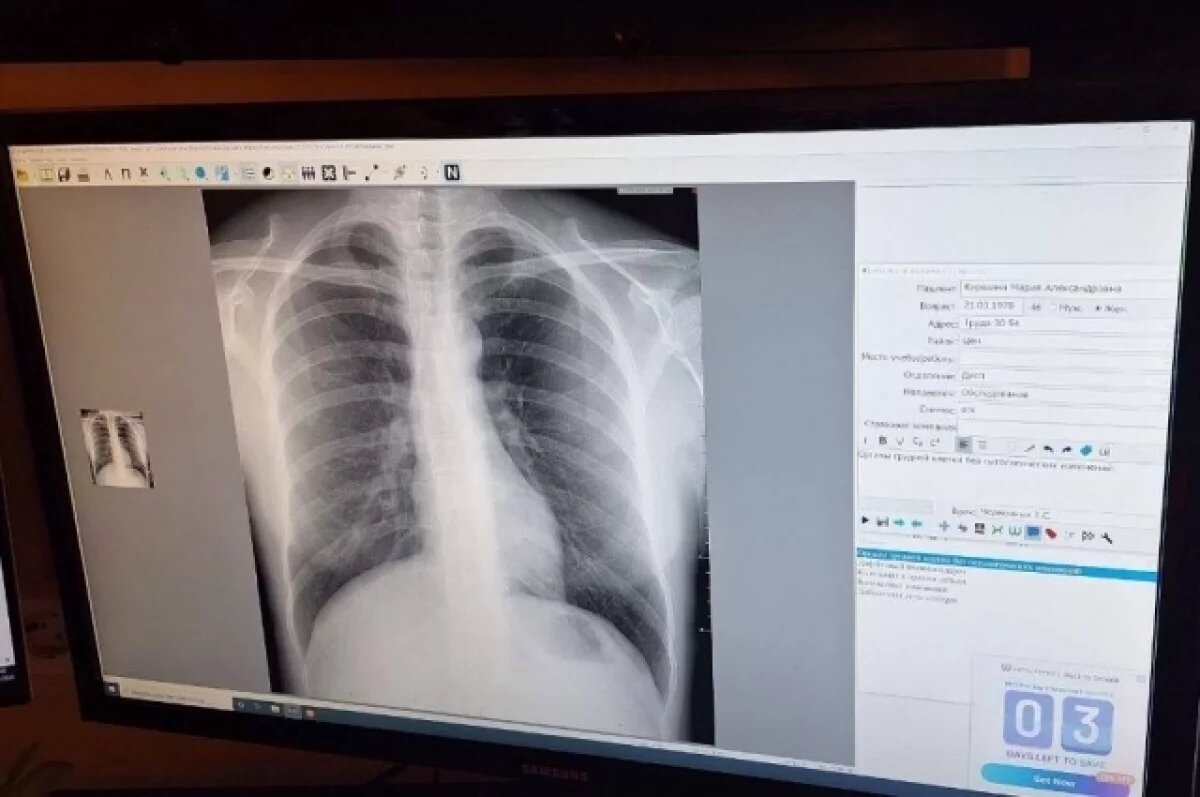

В Челябинской городской клинической больнице № 1 начали использовать искусственный интеллект для интерпретации рентгеновских снимков. Компьютерное зрение самостоятельно помечает тревожные участки красным цветом при подозрении на злокачественные новообразования, а доброкачественные — зеленым. Об этом сегодня, 18 сентября, сообщило министерство здравоохранения Челябинской области.

Программа анализирует снимки и выдает детальную характеристику в течение нескольких секунд. Врачу остается на основе этих предпротоколов составить конечное заключение.